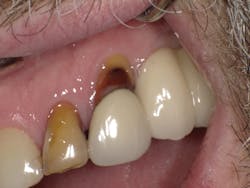

Case Three is a challenging crown repair on a medically compromised patient. The preoperative image shows decay at the buccal margin of an anterior abutment to a bridge (figure 11). Following excavation with the Lite Touch laser (figure 12), we decided to use Futurabond U in a self-etch technique followed by layering Admira Fusion in two increments. The first increment was an opaque layer, using shade OA2 to attempt to block out the gray margin of the porcelain-fused-to-metal crown (figure 13). After light-curing that layer, we applied shade A1 and light-cured and polished the restoration, achieving a highly esthetic result given the difficulty of the situation (figure 14).

Figure 11

Figure 12

Figure 13

Figure 14